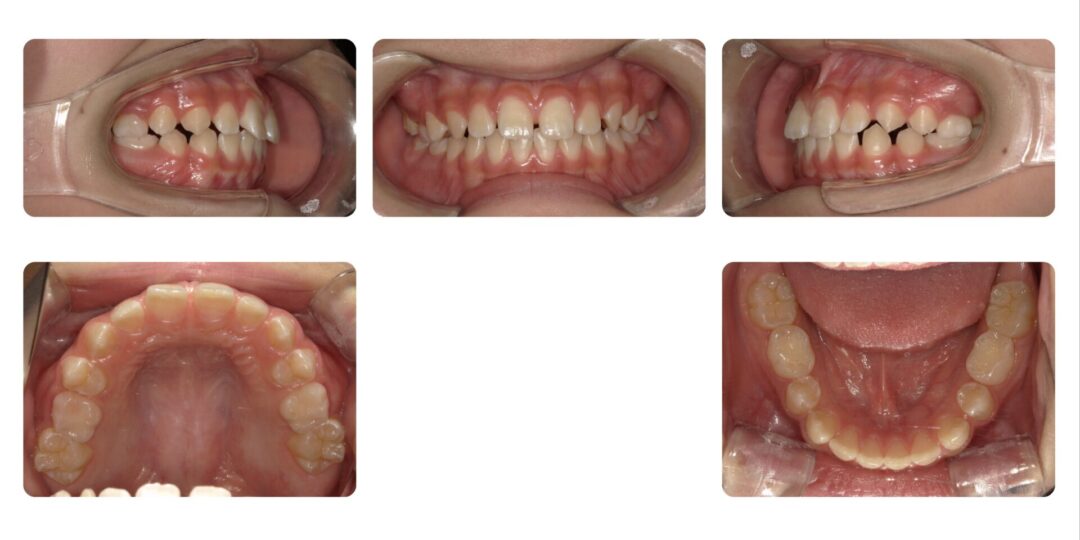

矯正治療前

第一期治療 上下拡大床による歯列矯正

初診時9歳